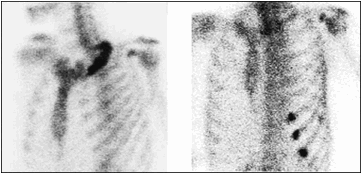

骨転移の診断:骨シンチグラフィ

従来、骨シンチグラフィは、感度は高い(異常の検出はよく出来る)が、特異度があまり高くない(異常がどのような原因で生じているのか分からない)検査と言われています。我々の施設では、パターン認識の要素を診断時に加味することにより成績が向上しています。その一端を紹介します。骨への転移と良性の変化を鑑別するポイントは、下記などです。

骨シンチグラフィの読影法

- 骨転移は骨髄で増殖するため骨の長軸に沿った形で拡がりやすい。一方、外傷は骨の長軸に垂直に現れやすい。

- 骨転移は骨の中に生じる。変性は関節面に生じる。

- 骨転移は病変の中央部が腫瘍に置き換わっていることが多いために中央部が欠損になり周囲に集積増加を認めることが多く、ドーナッツ型になります。他の原因によるものは、中央部の集積が高いことが多くあります。但し、前立腺がんによる骨転移など造骨型の骨転移は例外です。

- 骨転移は、左右非対称であることが多い。

- 骨転移の分布は、赤色骨髄の分布もしくはバトソン静脈叢の分布と一致することが多い。すなわち、体幹部および四肢の近位部に多い。

- 多発性であることが多い。